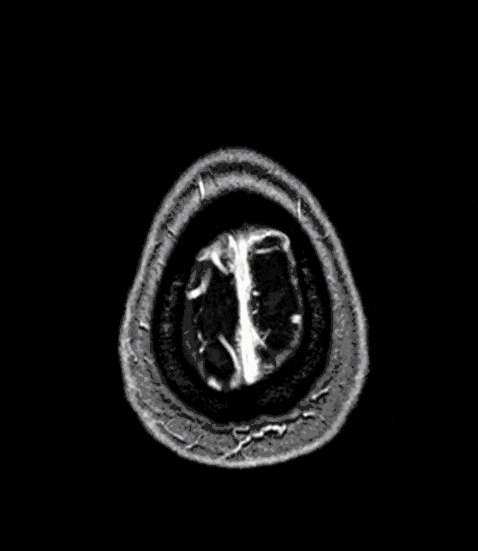

Cavernoma - Cavernous Malformation (CM)

Similar to other angiomas, Cavernomas or Cavernous Malformations (CM) can also lead to hemorrhages with neurological deficits or epilepsy. Often, however, cavernomas are completely asymptomatic and are discovered by chance on magnetic resonance imaging.

A thorough evaluation of clinical and neurological symptoms with analysis of imaging findings (MRI, fMRI) are essential for a targeted personal consultation and, if necessary, the best possible treatment of cerebral and spinal cavernomas.